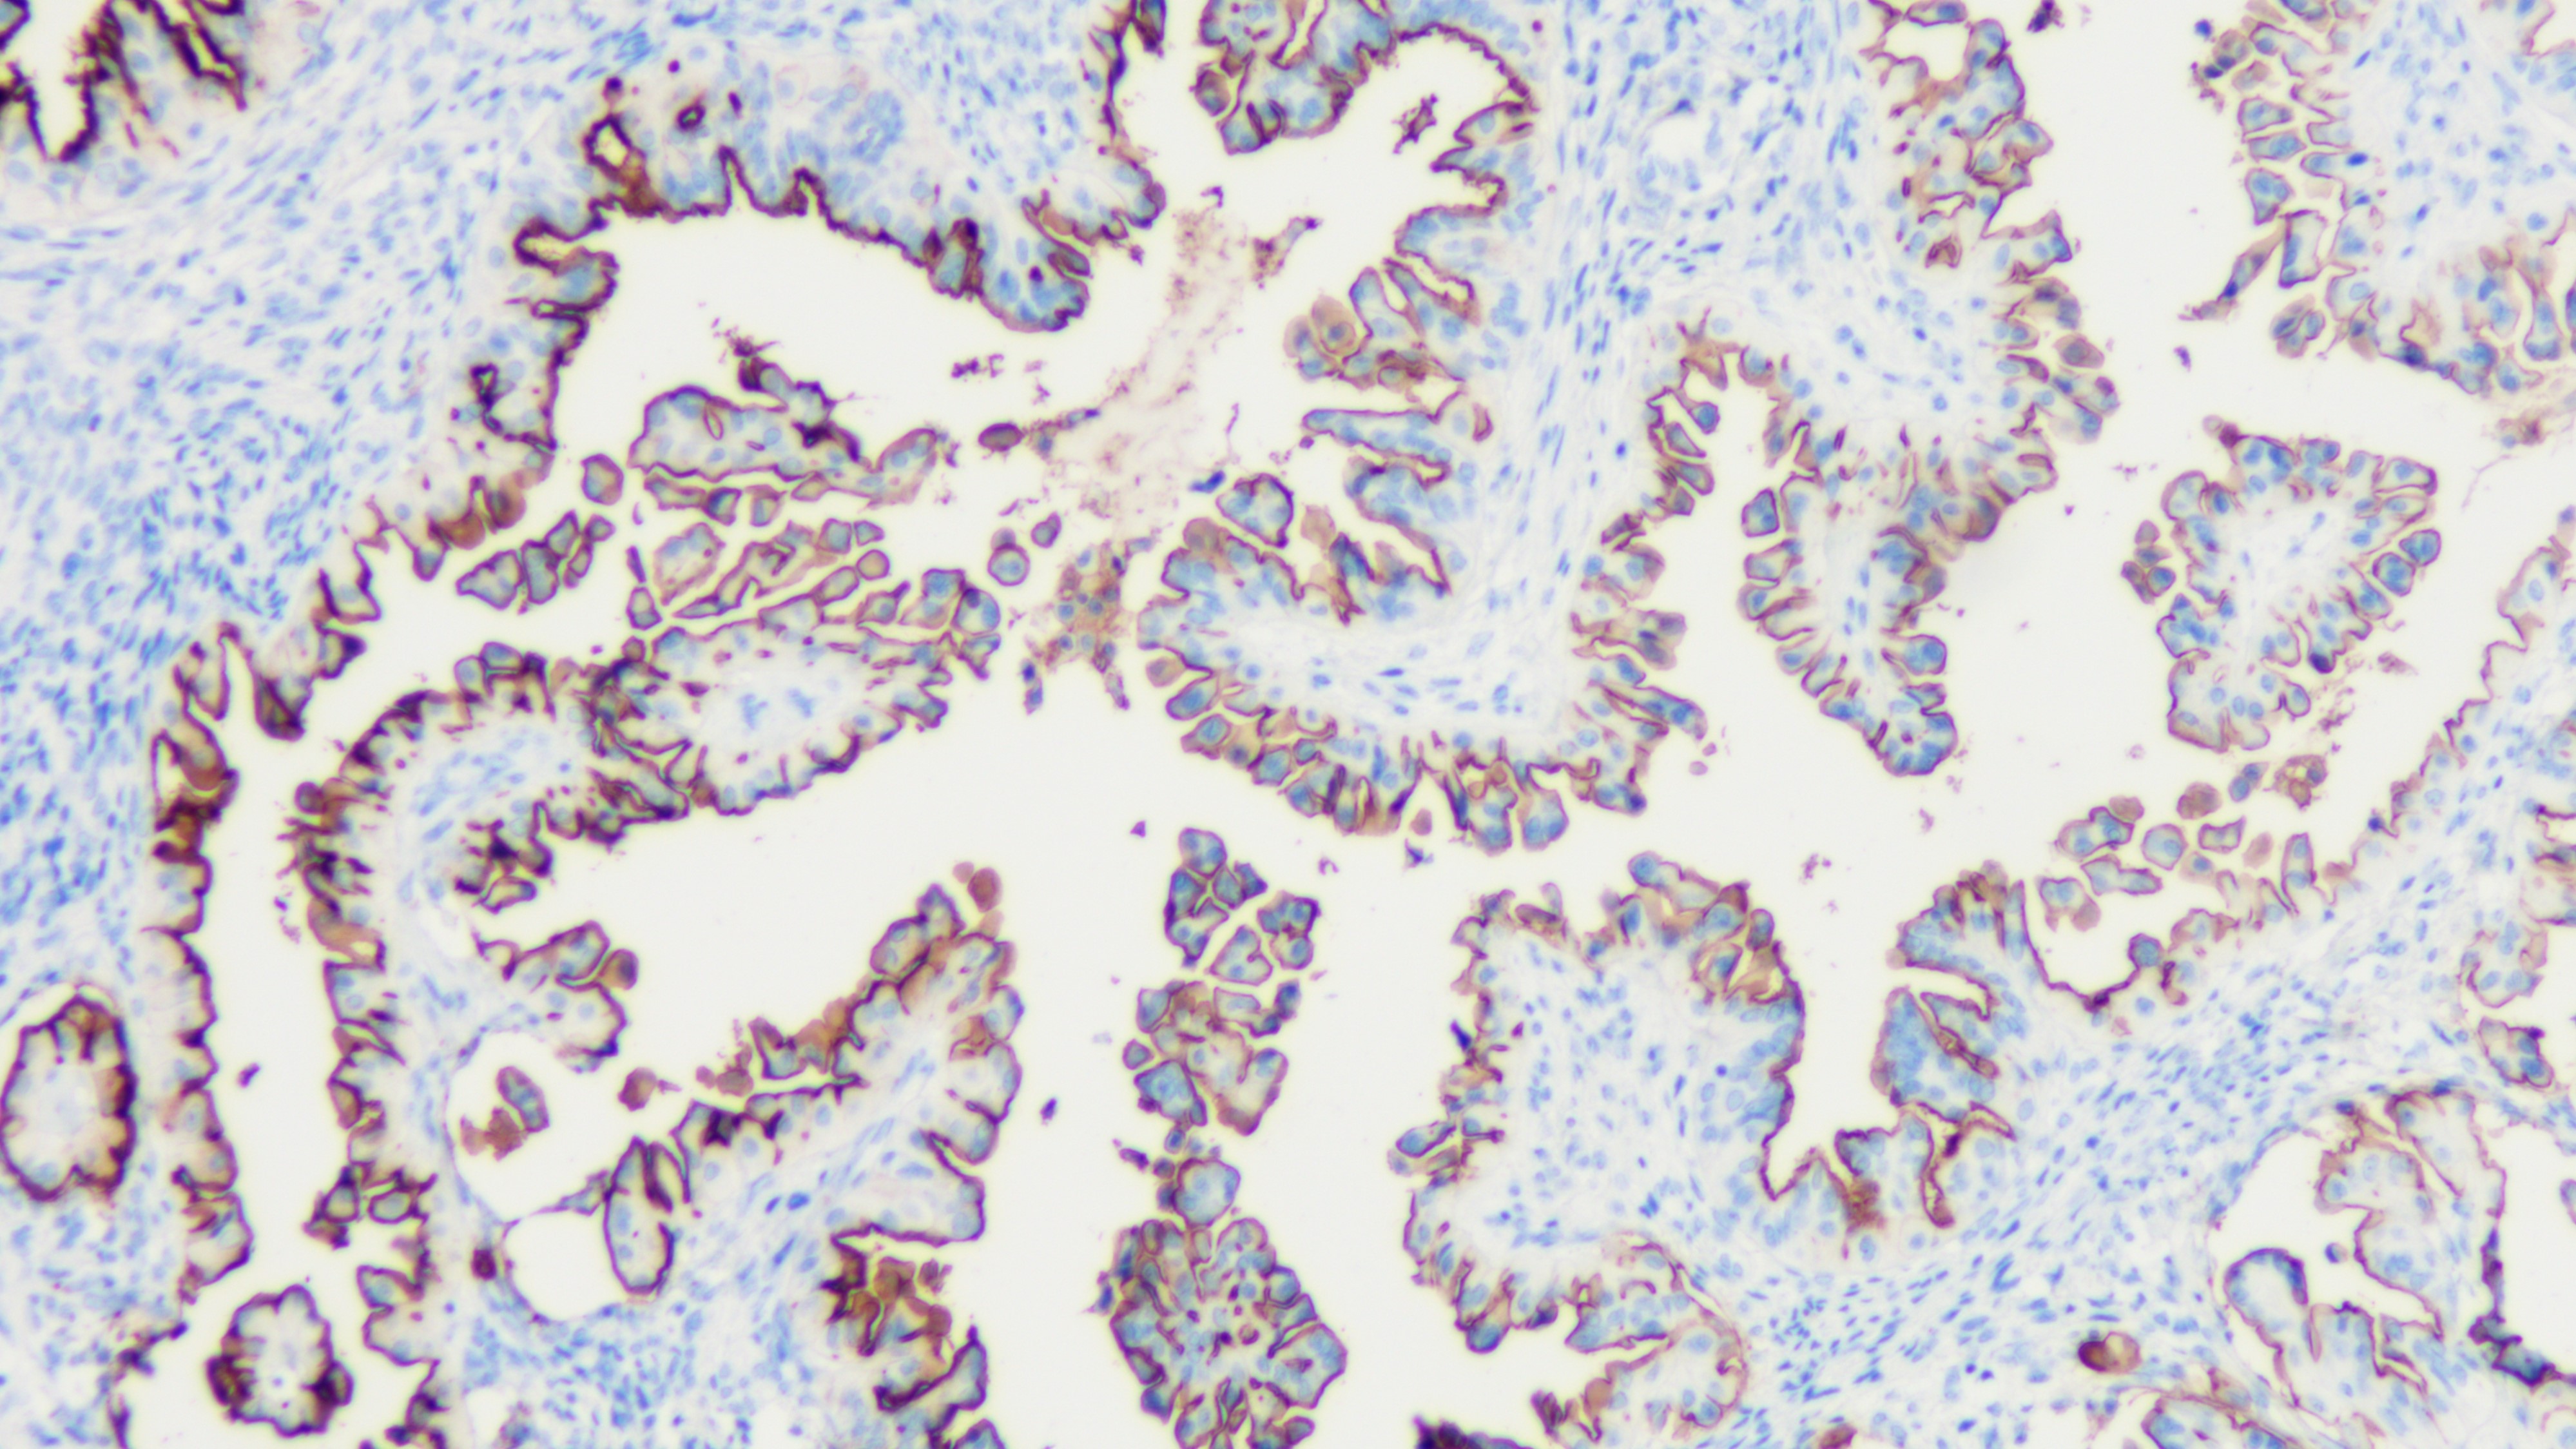

SOX-11是一种核转录因子,定位于2P25.3,主要和胚胎神经发育相关。它主要包含了两个功能区,位于蛋白N端的HMG DNA结合区域,以及位于C端的反式激活区。SOX-11的表达对于胚胎神经系统以及组织重构都至关重要,它在人体胚胎神经系统的发育过程中都有正常表达,并且对于神经突的生长和神经元的存在都是必须的。在18-25周的胎儿组织中,SOX-11主要表达在脑部。中枢神经外,SOX-11主要在上皮与间皮组织的交界处表达。SOX-11在正常成人的组织中不表达。SOX-11在多数套细胞淋巴瘤中存在过表达,包括罕见的cyclin D1-情况。SOX-11目前主要被用于鉴别套细胞淋巴瘤。

套细胞淋巴瘤